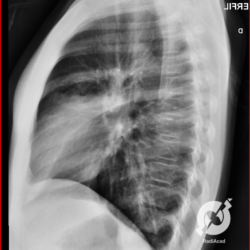

Os agentes etiológicos infecciosos são variados (bactérias, vírus, fungos, parasitas…), mas o que ocorre nos pulmões durante uma infecção por qualquer tipo de agente é a substituição do ar alveolar por secreção (pus, muco, eventualmente sangue ou necrose…) e com isso a manifestação radiográfica vai ser a mesma já que todas estas secreções apresentam a mesma densidade radiográfica: partes moles.

E o nome dado a esta alteração radiográfica que corresponde à substituição do ar alveolar por líquido é a consolidação alveolar.

Uma consolidação alveolar é, por definição, uma opacidade (imagem densa, branquinha) homogênea ou às vezes heterogênea (pela presença de calcificações ou cavidades), de limites mal definidos, exceto quando toca a pleura da parede ou das cissuras pulmonares. É um termo usado tanto em radiografia, como em tomografia computadorizada. Na tomografia, um outro termo é usado: vidro fosco, que é uma opacidade (branquinha mas não tanto como a consolidação), que borra o pulmão mas deixa ver os vasos de permeio (igual bigode de adolescente: dá pra ver todo o fundo).

Nós vamos mostrar aqui um pequeno apanhado de pneumonias de variados agentes, em diversos segmentos e lobos pulmonares, com extensões variadas. O objetivo é identificar o padrão radiológico de consolidação alveolar e não determinar o agente infeccioso, isso vai ser assunto para mais adiante. Aliás já antecipo que é fundamental saber localizar a lesão, porque alguns destes bichos gostam de determinados segmentos, alguns tumores também têm as suas preferências, então localização é fundamental. Se localização não fosse importante, um apartamento na beira do mar sairia o mesmo preço de um apartamento de frente pra BR-101, concordam?

Seguem alguns dos nossos casos de pneumonia para vocês treinarem os olhos e não se apavorarem nos plantões.